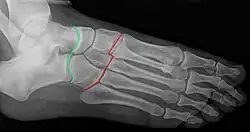

François Chopart est notamment connu pour avoir mis au point une technique d'amputation, longtemps appliquée sur les champs de bataille, consistant à sectionner le pied non pas à travers l'os, mais en suivant les articulations talo-naviculaire et calcanéo-cuboïdienne (qui ont d'ailleurs été regroupées sous la dénomination d'articulation de Chopart en hommage au chirurgien).